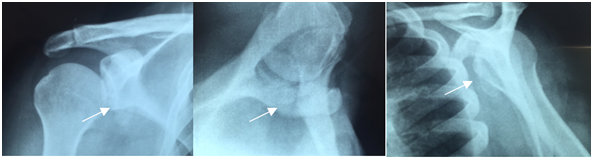

The patient was a 47-year-old man who worked as a sales representative. He presented with a history of falling down stairs two years previously, at which time he sustained trauma to the right shoulder. Since then, he had experienced pain and functional impairment, which he described as being unable to perform intimate hygiene or grab a wallet from his back trouser pocket and difficulty in using his arm when above shoulder height. The patient did not seek medical assistance at the time of the trauma because he did not have medical insurance and did not want to be treated in the public healthcare sector. Our initial physical examination showed a normal but painful range of movement; with positive tests for evaluate subscapularis tendon injury (e.g., bear-hug, Gerber, abdominal compression and lift-off tests). His DASH (Disabilities of the Arm, Shoulder and Hand) score was 60, his UCLA (University of California at Los Angeles) Shoulder Score was 16, his SF-36 (Short Form Health Survey) Score was 32.7 and his visual analog scale (VAS) score was 10. Shoulder x-rays revealed an avulsion fracture of the lesser tuberosity of the proximal humerus (Figure 1). Magnetic resonance imaging was done to support this, which confirmed the diagnosis of an isolated displaced fracture of the lesser tuberosity (Figure 2).

Figure 1 Preoperative radiographs showing a deviated fracture of the lesser tuberosity, which was at the level of the glenoid (white arrow).